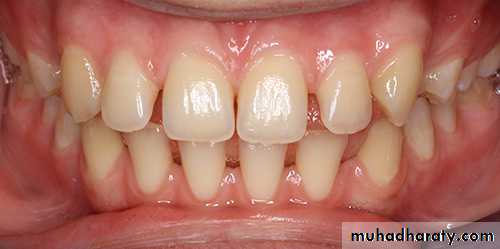

2- Anomalies of the size of teeth

a- Microdontia which may lead to spacingb- Macrodontia which may lead to crowding